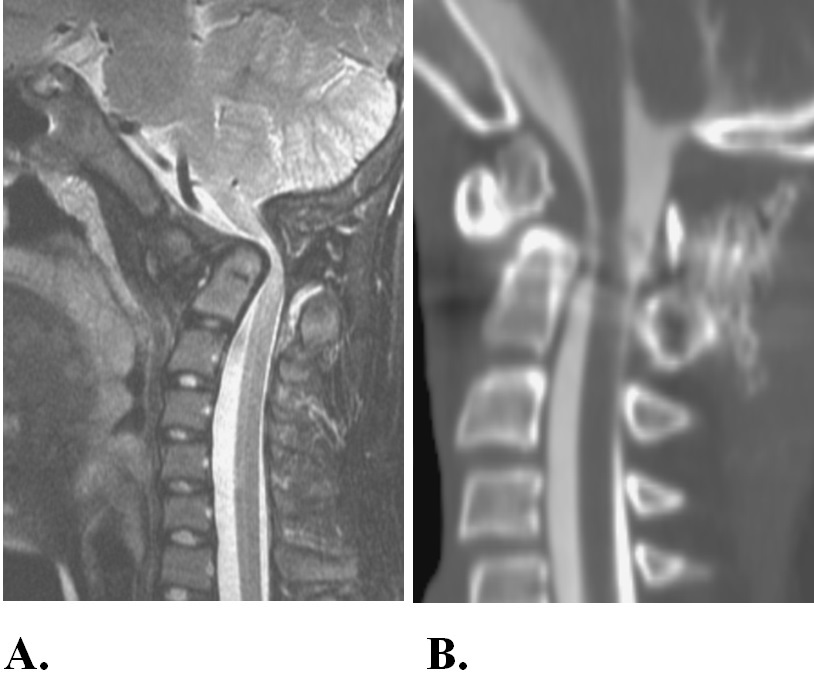

Chính vì những ưu điểm trên, ngày nay trên thế giới, kỹ thuật của Harms đã được coi là sự lựa chọn tối ưu cho các trường hợp mất vững khớp đội - trục. Từ năm 2011, Khoa Ngoại thần kinh - Hubet com cá cược thể thao Trung ương Hubet7788 trò chơi trực tuyến 108 đã triển khai kỹ thuật này. Hiện nay, kỹ thuật đã được áp dụng thường quy cho các mất vững khớp đội - trục do các nguyên nhân khác nhau: Chấn thương, viêm khớp dạng thấp, lao... mang lại kết quả tốt.

Hình ảnh minh họa

Hình 1. Hubet5555 chuẩn mã hóa SSL quốc tế nam, 33 tuổi. Năm 13 tuổi, đá bóng ngã, sau ngã liệt tứ chi, phục hồi dần. Trước khi vào viện 3 năm thấy tứ chi yếu dần. Vào viện trong tình trạng bại nặng tứ chi, tiểu qua sonde, khó thở nhẹ. Trên phim X-quang (A) có mất vững, biến dạng khớp đội - trục. Trên cộng hưởng từ (B), ống sống bị hẹp, tủy sống bị đè ép mức độ nặng.